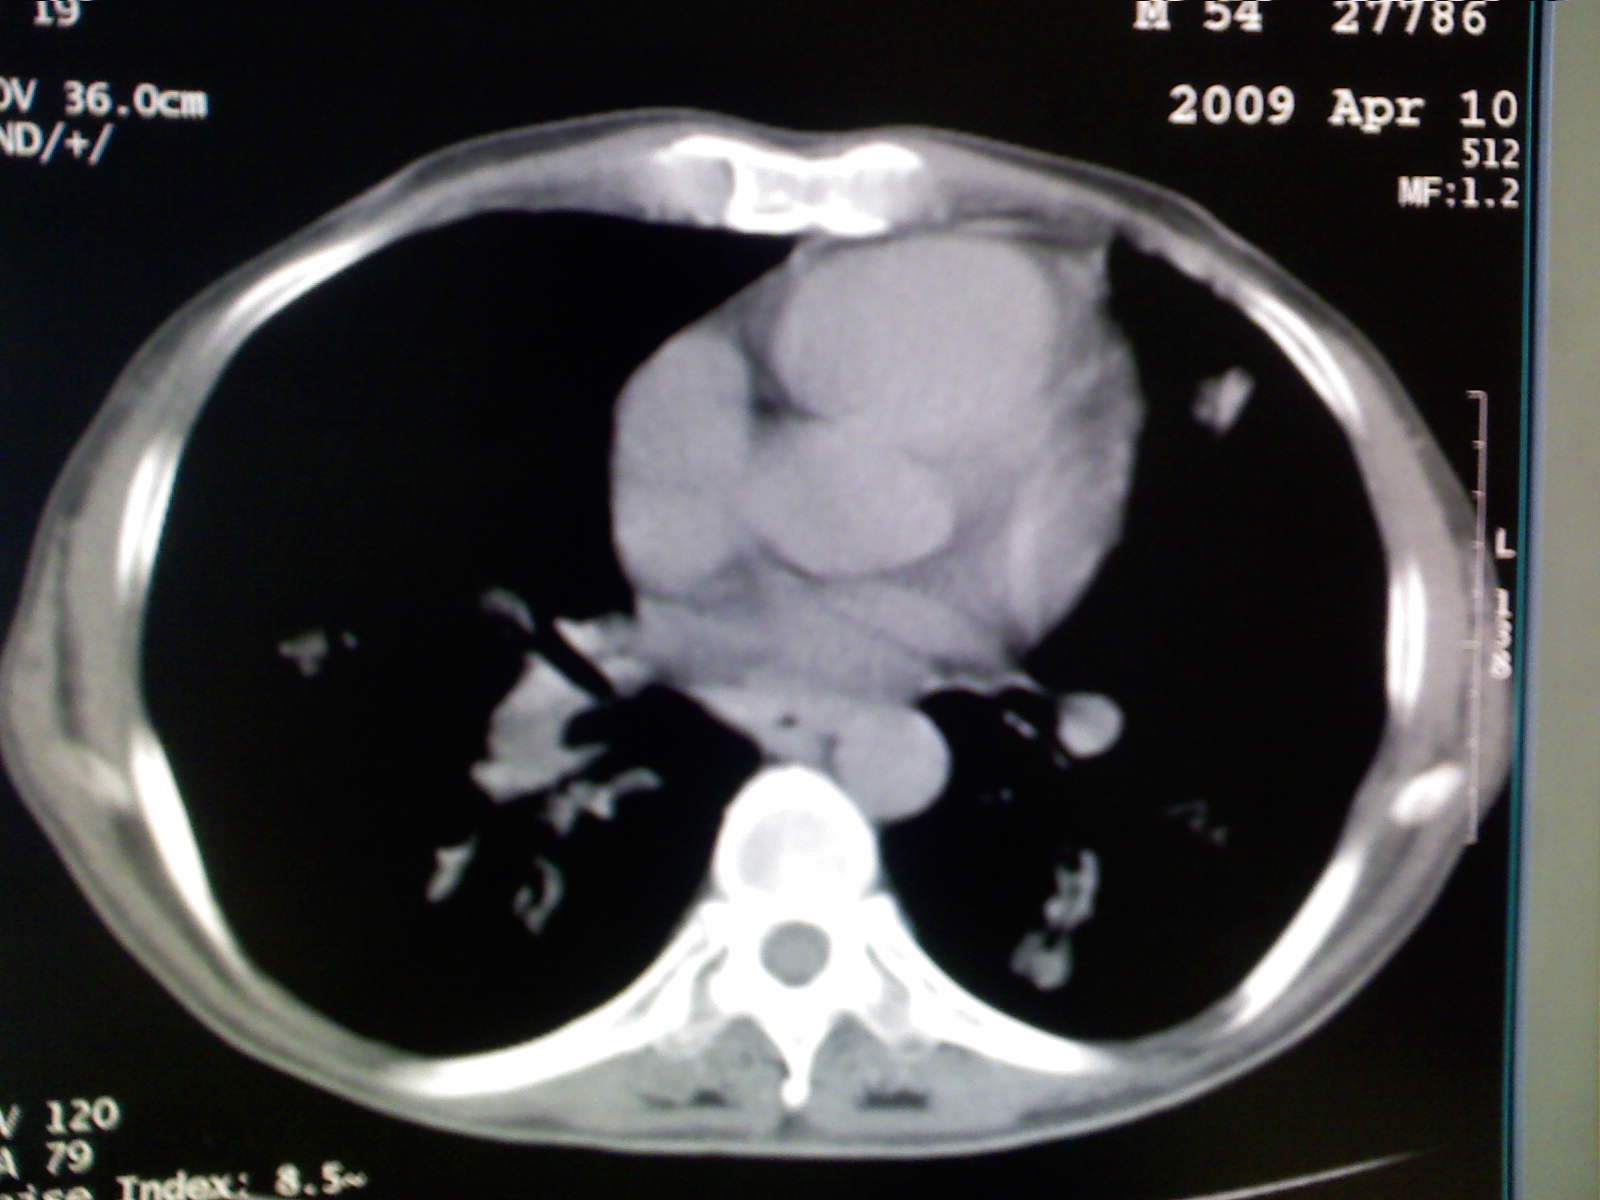

以下是引用卜一在2009-4-11 15:50:00的发言:[br]双肺继发性肺结核伴空洞形成,不排除合并霉菌感染!(病灶呈多形态 多特征 散在分布)。另:合并支气管扩张征伴感染!

以下是引用主力军在2009-4-11 15:55:00的发言:[br]两肺继发性肺结核可能性大。

以下是引用康鹏在2009-4-11 16:30:00的发言:[br]双肺继发性肺结核伴空洞形成合并感染[br]支气管扩张合并感染